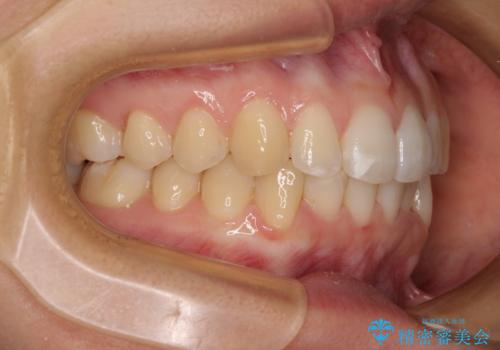

【モニター】前歯のデコボコとクロスバイト インビザラインによる矯正治療

- 上下のクロスバイトと前歯のデコボコを気にして来院された患者様です。

インビザラインを用い、IPR(歯と歯の間を削る)と歯列全体を拡大させることで、歯並びを整えていくこととしました。

下の歯が隠れてしまうほどでしたが、深い咬み合わせも改善され、顎への負担も軽減されました。